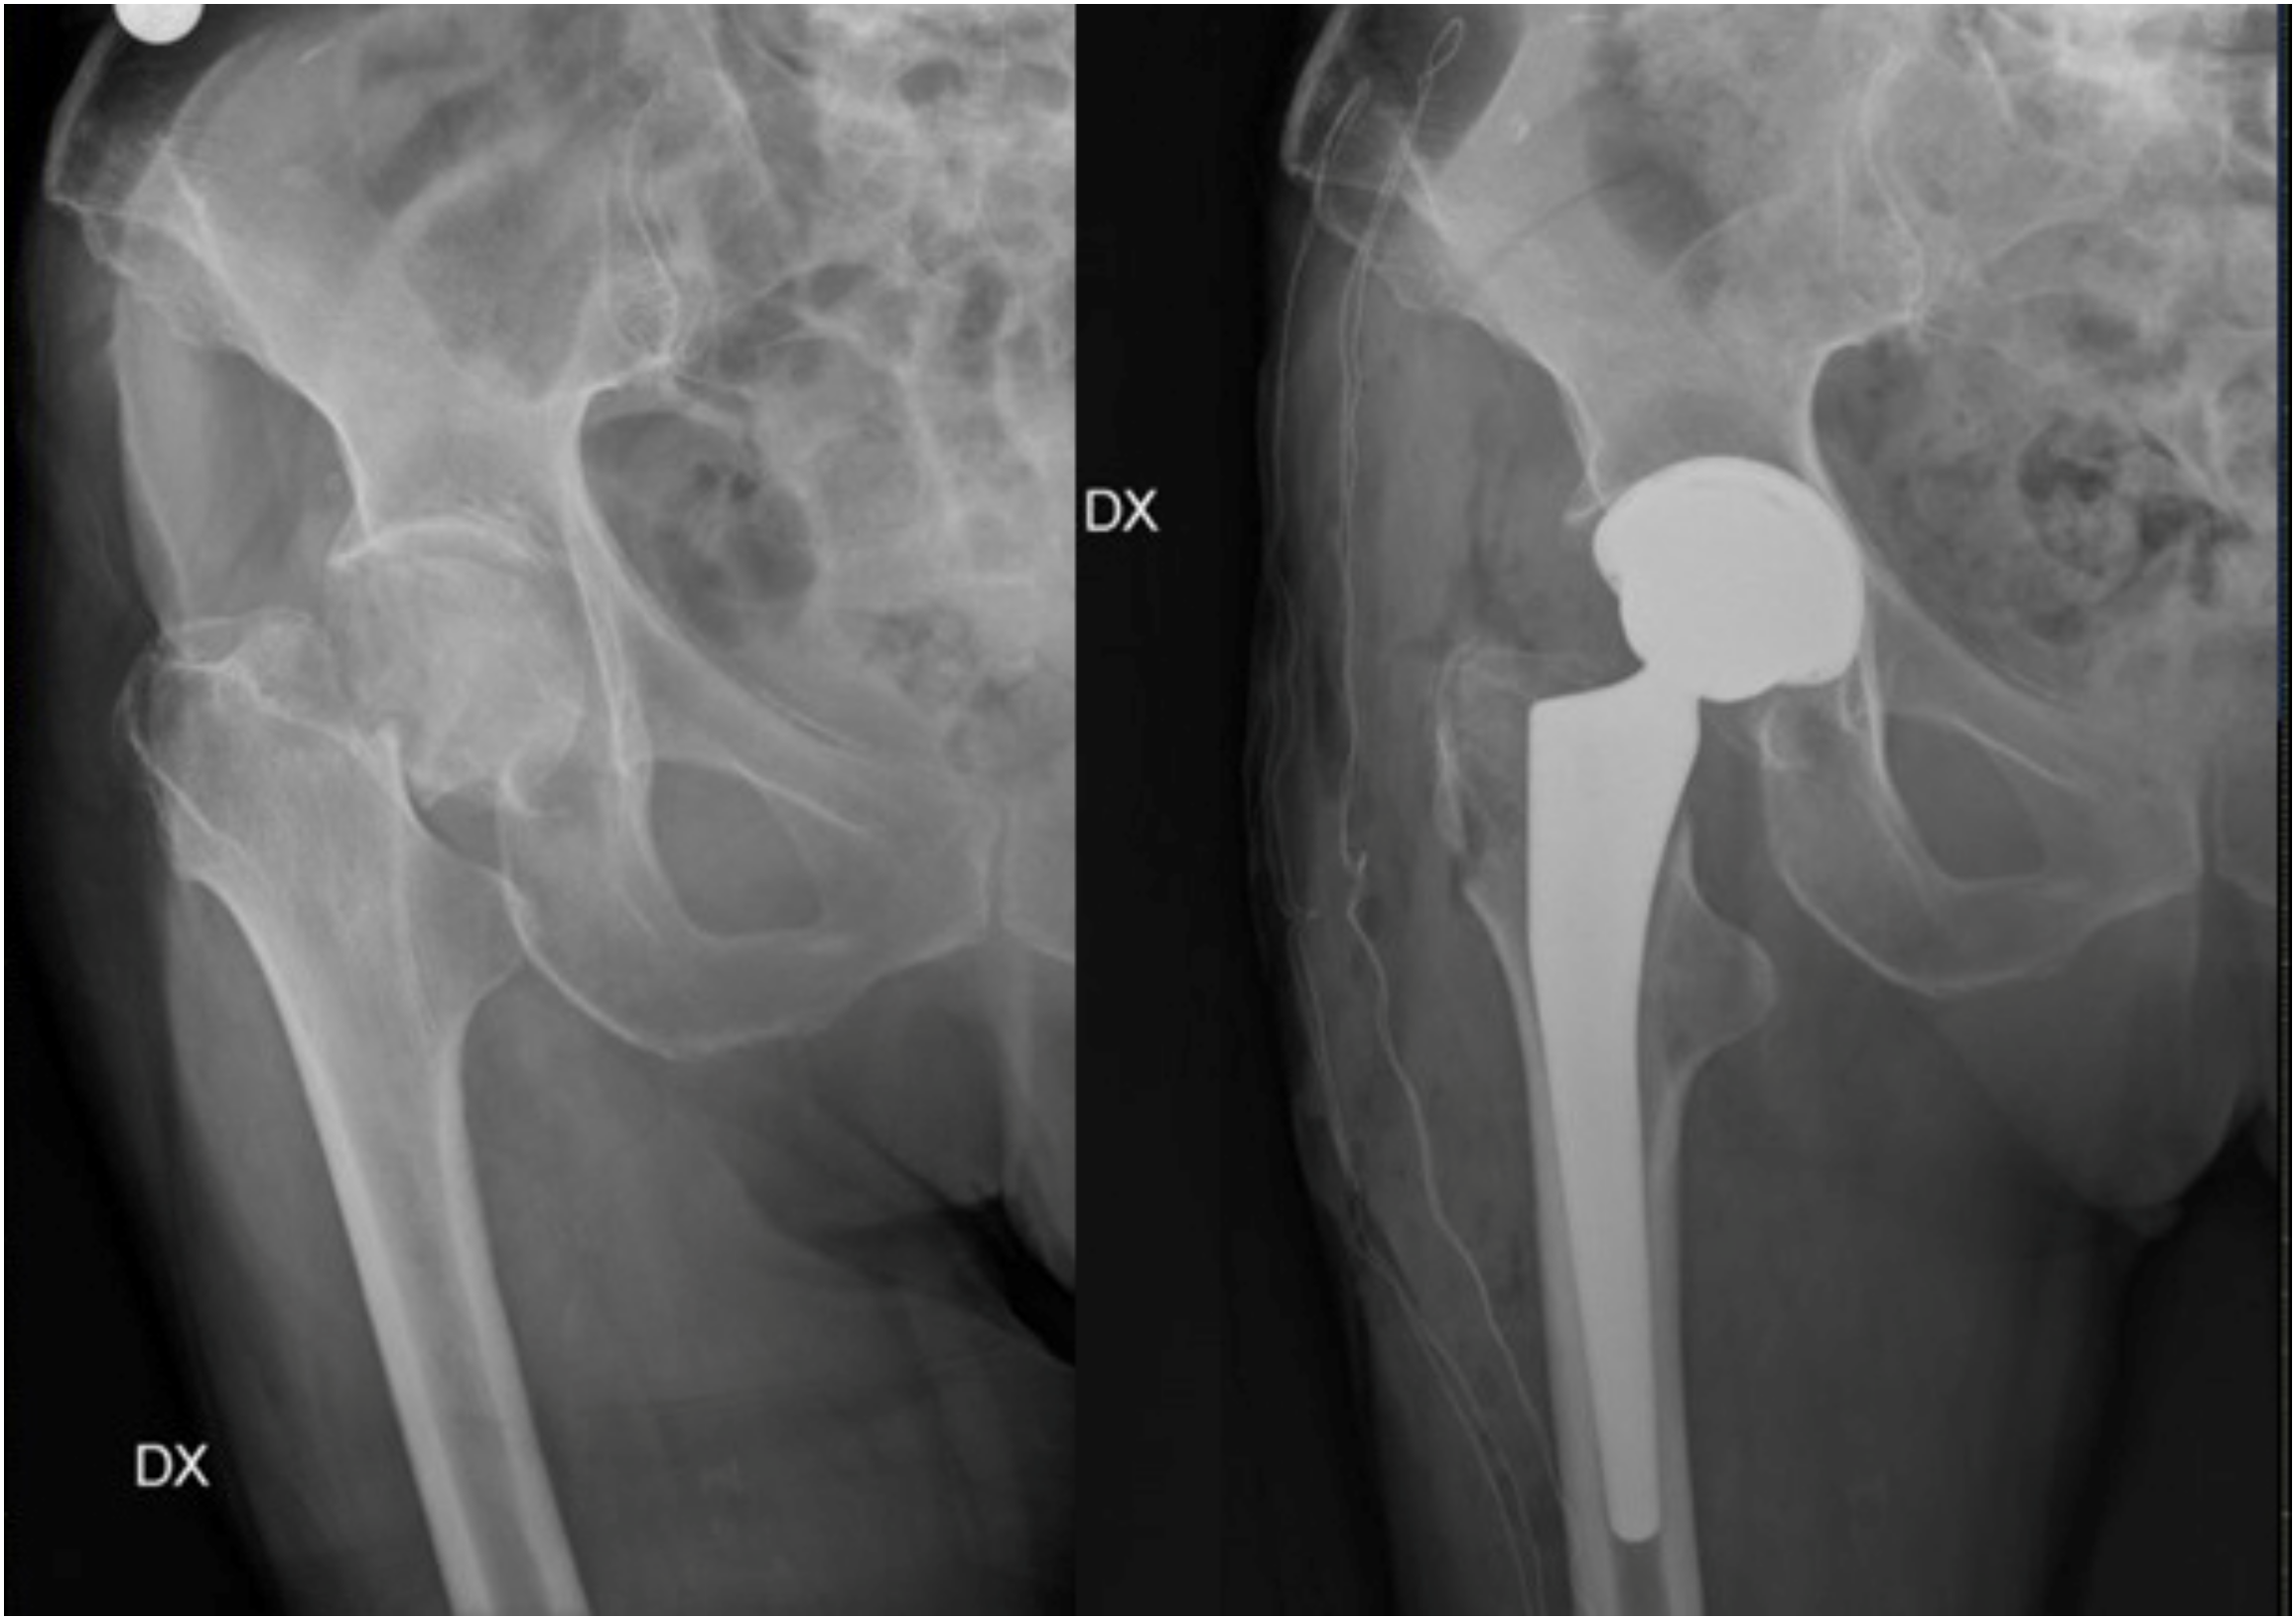

- Parker, M.J.; Gurusamy, K.S.; Azegami, S. Arthroplasties (with and without bone cement) for proximal femoral fractures in adults. Cochrane Database Syst. Rev. 2010, 16, CD001706. [Google Scholar] [CrossRef]

- Lowe, J.A.; Crist, B.D.; Bhandari, M.; Ferguson, T.A. Optimal treatment of femoral neck fractures according to patient’s physiologic age: An evidence-based review. Orthop. Clin. N. Am. 2010, 41, 157–166. [Google Scholar] [CrossRef]

- Braun, K.F.; Hanschen, M.; Biberthaler, P. Frakturendoprothetik der medialen Schenkelhalsfraktur. Der Unfallchirurg 2016, 119, 331–345. [Google Scholar] [CrossRef]

- Baker, R.P.; Squires, B.; Gargan, M.F.; Bannister, G.C. Total hip arthroplasty and hemiarthroplasty in mobile, independent patients with a displaced intracapsular fracture of the femoral neck. A randomized, controlled trial. J. Bone Jt. Surg. Am. 2006, 88, 2583–2589. [Google Scholar] [CrossRef]

- Bhandari, M.; Einhorn, T.A.; Guyatt, G.; Schemitsch, E.H.; Zura, R.D.; Sprague, S.; Frihagen, F.; Guerra-Farfán, E.; Kleinlugtenbelt, Y.V.; Health Investigators. Total Hip Arthroplasty or Hemiarthroplasty for Hip Fracture. N. Engl. J. Med. 2019, 381, 2199–2208. [Google Scholar] [CrossRef]